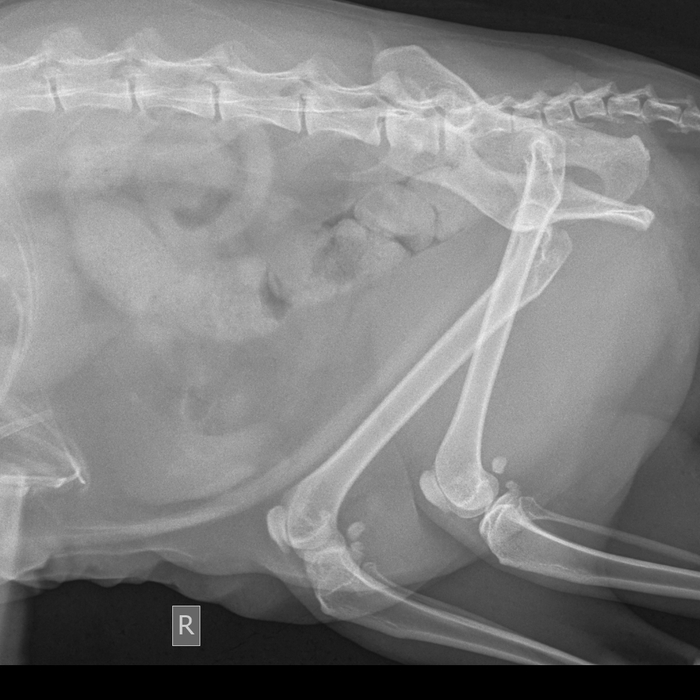

Кот 4 дня назад ухитрился сдвинуть створку окна на балконе и вышел с 5 этажа. Состояние норм, кушает замечательно, УЗИ особых проблем не показало (ничего себе не порвал, но, конечно, отбил). Проблема в том, что лечимся мы сейчас в одной клинике, но с травмой поехали сначала в другую, круглосуточную. И рентген коту делал вьюнош молоденький. Сказал, мол, все хорошо, кости целы. И вот, смотрю я на снимок и мне, чайнику, мерещится, что обе бедренные конкретно так треснутые в районе таза. Кот матерится, но ходит (на задние лапы опираться не торопится, ругается). И я хочу спросить - оставить как есть (пьем мелоксидил) или хирургически что-то предпринять стоит? Или мне эти трещины просто померещились?